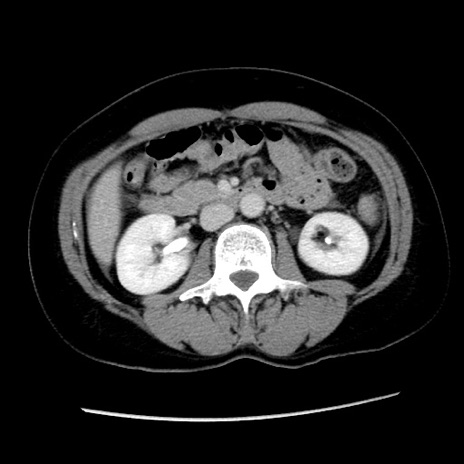

症例10(横断像)

【症例】 50歳代女性

【主訴】 腹痛

【現病歴】前日生レバーを食べた。今朝に排便あり。 昼前に突然発症の腹痛を生じ、当院救急外来を受診した。

【身体所見】 意識清明、腹部:平坦、軟、下腹部やや左を中心に圧痛・反跳痛あり、筋性防御あり